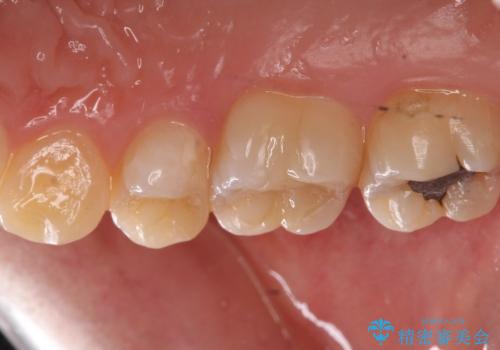

銀歯を白くしたい

- 奥歯の銀の詰め物を白くしたいとのことで来院されました。

- 右上7 セラミックインレー 77,000円費用は治療当時の料金となります

今回は大きな虫歯もなかったため、1回当たり30分程度の治療時間で計2回の来院回数で治療を終えることができました。